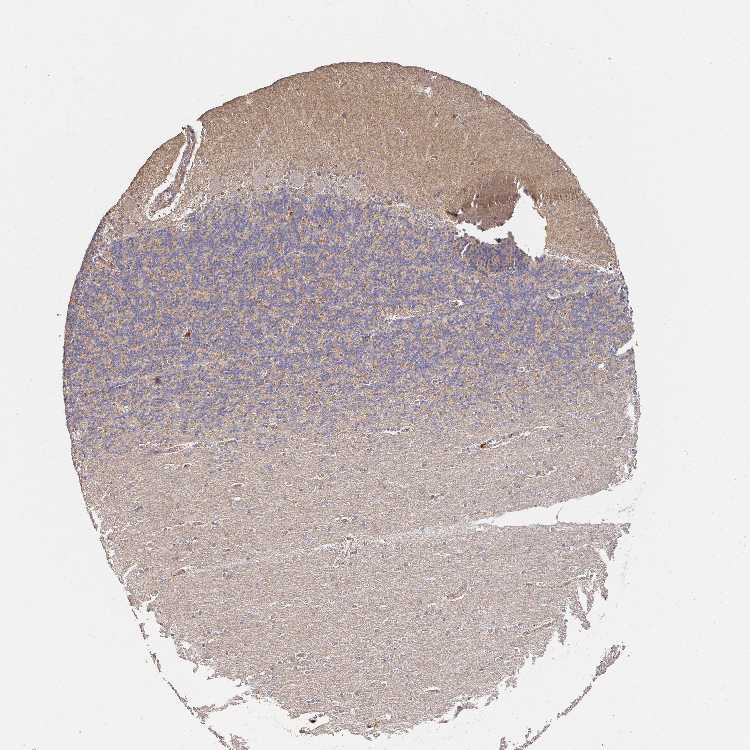

BRAIN CEREBELLUM Show tissue menu

CEREBELLUM - Expression summary

CEREBELLUM - Antibody stainingi

Antibody staining in the annotated cell types in the current human tissue is reported as not detected, low, medium, or high, based on conventional immunohistochemistry profiling in selected tissues. This score is based on the combination of the staining intensity and fraction of stained cells.

Each image is clickable and will lead to virtual microscopy that enables deeper exploration of all samples and also displays staining intensity scores, fraction scores and subcellular localization as well as patient and tissue information for each sample.

Antibody HPA038521Antibody HPA038522

Purkinje cells Not detectedMedium

Cells in granular layer MediumMedium

Cells in molecular layer Not detectedNot detected